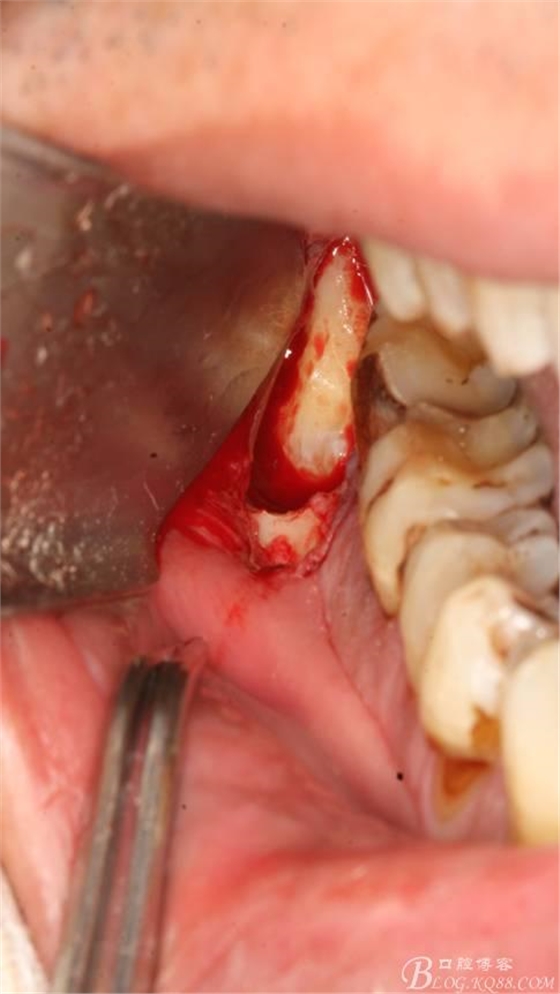

4.縱分牙根和牙冠

5.取出牙根